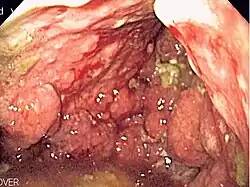

| Endoscopic image of linitis plastica, where the entire stomach is invaded with stomach cancer, leading to a leather bottle like appearance | |

Linitis plastica (sometimes referred to as leather bottle stomach) is a morphological variant of diffuse stomach cancer in which the stomach wall becomes thick and rigid.[1]